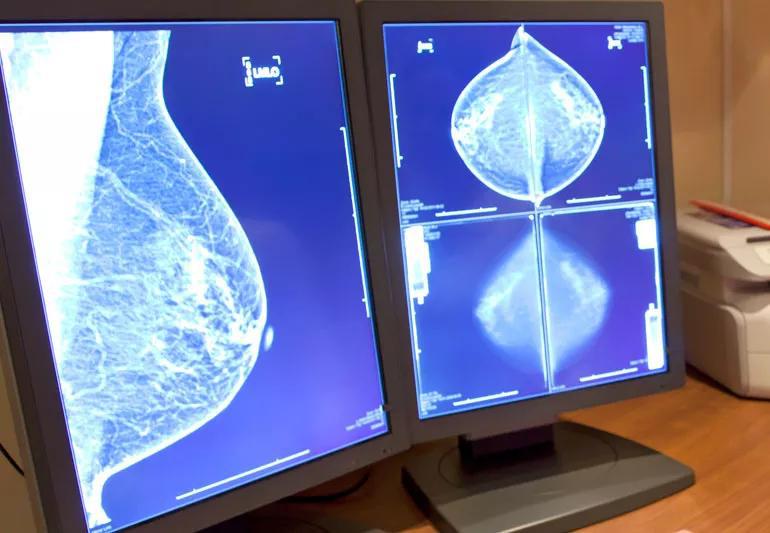

“We saw something on your mammogram and want to check it out.” The words every woman dreads to hear.

But what if your physician tells you that your mammogram and follow-up breast biopsy shows pseudoangiomatous stromal hyperplasia? What exactly does that mean?

Generally speaking, a lesion is a term used to describe anything abnormal. So when a radiologist sees a lesion on a mammogram, he or she flags it for follow-up, explains Downs-Kelly.